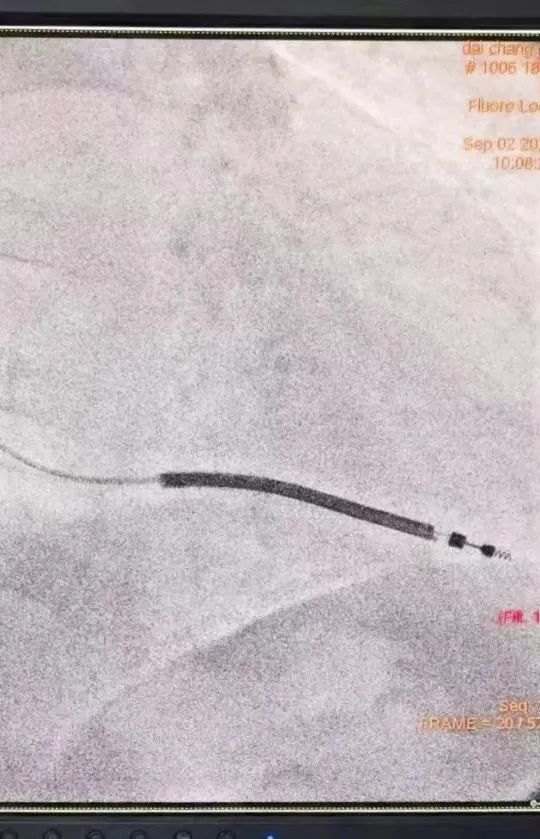

除颤电极放置,术中及术后第一天伤口